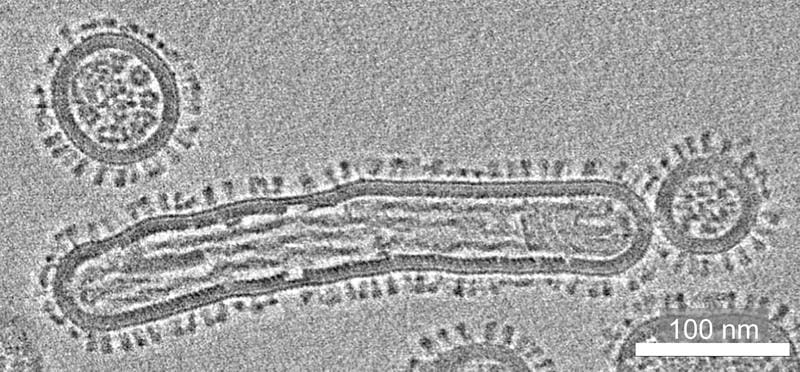

The Freiburg virologists develop and operate the network’s central laboratory platform. There, flu viruses are examined for their zoonotic potential, i.e. the ability to jump from animals to humans, using molecular biological and cell-based methods. These include genetic analyses, tests for virus replication and studies of the human immune response. The research is integrated into the structures of the University Hospital in order to improve diagnostics and prevention in patients.